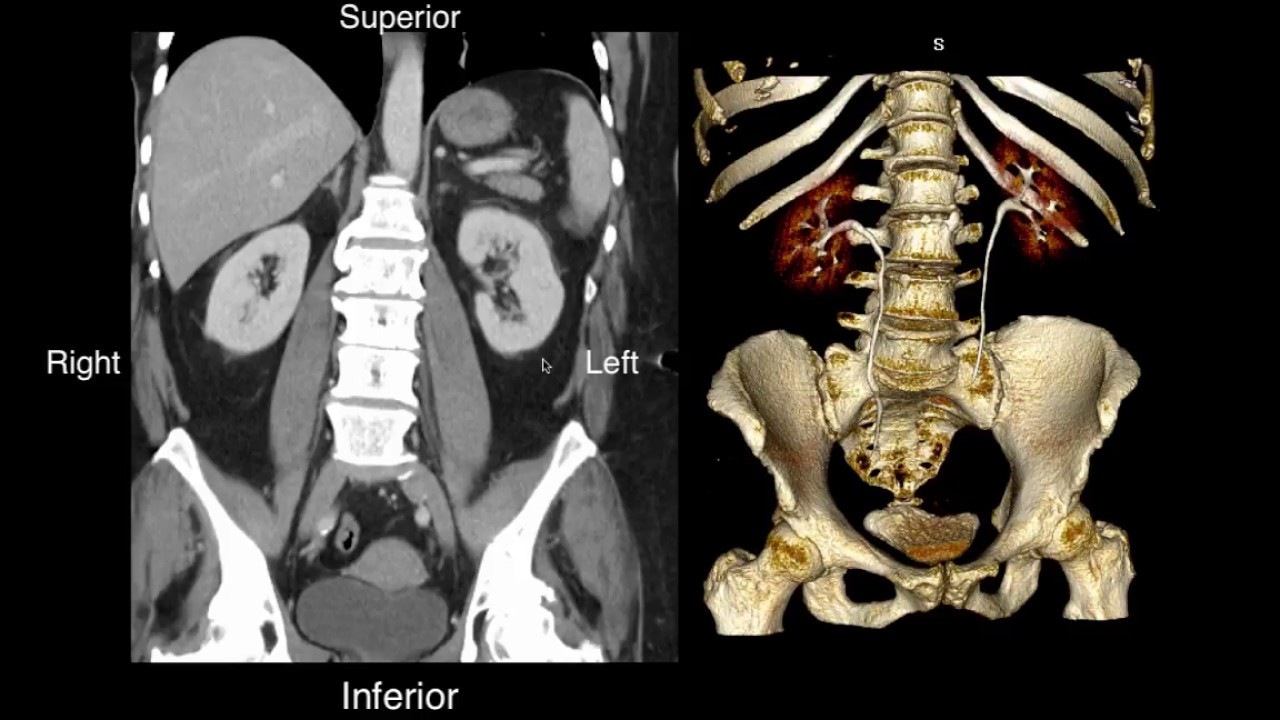

Bronchopulmonary segmental anatomy describes the division of the lungs into segments based on the tertiary or segmental bronchi. Anatomy of the thorax lungs and mediastinum ct interactive atlas of human anatomy using cross sectional imaging we have created an anatomical atlas of the chest and the mediastinum which is an interactive tool for studying the cross sectional anatomy of the normal thorax based on an enhanced multidetector computed tomography with helical angiography of the thorax axial plane. Ct of the chest lung windows axial anatomy.